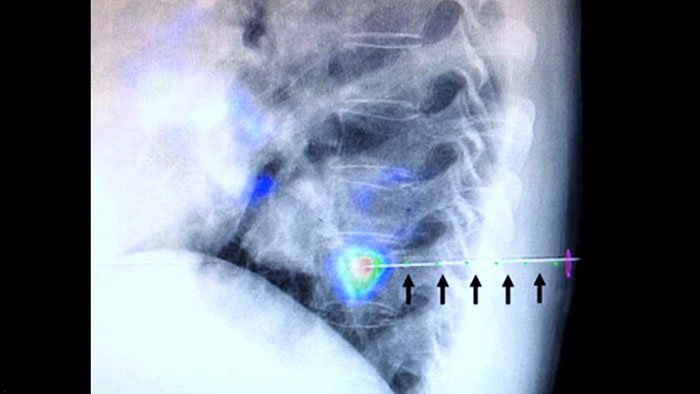

XperGuide proporciona una orientación por imágenes en tiempo real extremadamente preciso de cada aguja a una posición objetivo mediante la superposición de trayectorias preplanificadas con imágenes fluoroscópicas3.

La heterogeneidad de la lesión y la falta de notoriedad limitan la calidad de las muestras, así como la viabilidad de las biopsias cuando se realizan mediante ecografía o CT convencional. Con el aumento de la adopción de programas de detección en los pulmones, se han detectado cánceres pulmonares incipientes que se manifiestan como nódulos pequeños con mayor frecuencia que antes. Se observó que el 14.5% de una población seleccionada tenía nódulos ≤10 mm1-2. Nuestra tecnología de navegación guiada por aguja con CBCT aumenta la precisión y permite la selección de lesiones más pequeñas (<=1 cm) o heterogéneas, con mayor precisión con menos reposicionamiento de la aguja y menos dosis que la TC convencional.